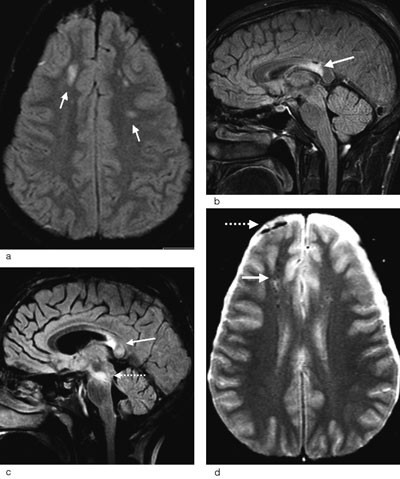

Diffus aksonal skade er ikke nødvendigvis diffus i sin utbredelse. Tvert imot forekommer disse lesjonene med et ganske typisk distribusjonsmønster. De fleste lesjoner er små (5 – 15 mm) og lokalisert til hvit substans og overgangen mellom grå og hvit substans i frontallappene og temporallappene (fig 2a). Ved kraftigere traumer kan det i tillegg påvises lesjoner i corpus callosum og i hjernestammen (fig 2b og c). Avhengig av hvilke strukturer som er omfattet av skaden, kan diffus aksonal skade graderes i grad 1 – 3 (tab 2) (25).

| Eventuelt i øvre cerebellare pedunkler |

Lesjonene er vanligvis multiple, ofte så mange som 15 – 20, og kan deles i hemoragiske og ikke-hemoragiske (25, 27). De ikke-hemoragiske lesjonene som forekommer hyppigst, representerer ødem i hjernevevet, mens de hemoragiske skadene trolig skyldes lekkasje av blod fra små kar som forløper langs aksonene og som rives over ved traumet. Blødningene er typisk punktformede, og de minste betegnes gjerne mikroblødninger (fig 2d).

MR-teknikker ved diffus aksonal skade

Hurtige T2-vektede spinnekkosekvenser og FLAIR-sekvenser er MR-teknikker som er følsomme for å påvise endringer i hjernens vanninnhold, og økt vanninnhold vises som områder med høyt signal. Ved FLAIR-sekvensen blir signalet fra det frie vannet i cerebrospinalvæsken undertrykket, og dette øker sensitiviteten for å oppdage ødem i hjernevevet ved diffus aksonal skade (fig 2a og c) (28).

Gradientekko T2*-vektede bilder (såkalt hemosekvens) er velegnet for å påvise blodnedbrytingsprodukter, og lesjoner med blodprodukter fremtrer som signaltomme områder (fig 2d) (25). Størrelsen på disse områdene er betydelig større enn selve blodansamlingen. Dette skyldes at de paramagnetiske blodproduktene forstyrrer magnetfeltet i et større område. Mens lesjonene forårsaket av ødem kan forsvinne etter dager eller uker, vil lesjonene som er forårsaket av mikroblødninger kunne bestå i måneder til år da nedbrytingsproduktene innleires i hjernevevet (14, 25).

Diffusjon. Diffusjonsvektet MR er en relativt ny teknikk som viser termisk bevegelse av vannmolekyler i vevet. Ved diffus aksonal skade inntrer endringer i vanndiffusjonen da aksonskade med kollaps av cellestrukturen kan gi endring av vannmolekylenes bevegelighet (29). Områder i hjernevevet med redusert diffusjon tyder på en irreversibel celleskade som vil føre til vevsnekrose (fig 3). Studier har vist at diffusjonsvektet MR er en mer følsom teknikk enn de tradisjonelle MR-sekvensene (27, 30). Siden blant annet mikroblødninger vil være lettere å påvise med andre MR-sekvenser, må diffusjonssekvenser likevel benyttes som et tillegg til, og ikke som erstatning for, de konvensjonelle teknikkene.